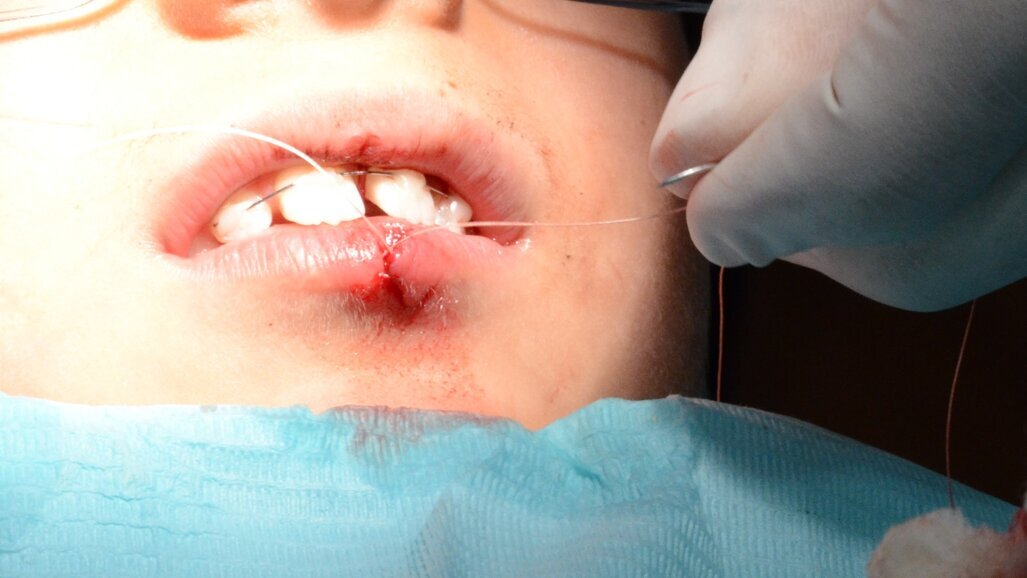

Within the hour, tooth 21 was gently replanted into the socket (Figure 6) and a flexible 0.5mm wire/composite passive splint of teeth #12, 11, 21, 22 was secured (Figure 7). We sutured the lacerated lower lip in multiple layers (mucosa, deep and superficial) using Vicryl® (Sizes 40 and 60) resorbable fine sutures (Figure 8 and 9). This took place after thorough debridement of the wound with physiological saline. Care was taken to assure alignment of the lip’s vermilion involved in the laceration.

Figure 8. Suturing of the lower lip laceration in three layers using fine resorbable sutures (Vicryl® Sizes 40 and 60).

Figure 9. Immediate post suturing. Notice the wound margins had been aligned so the vermilion was continuous.